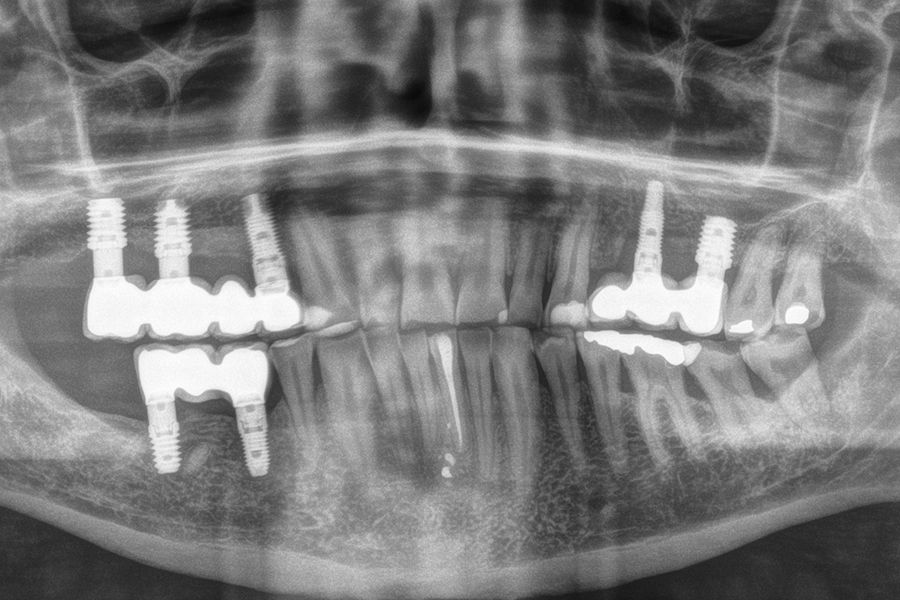

Material and method: We retrospectively recruited patients who attended our dental clinic with problems in different implant rehabilitations of an eminently mechanical nature (fracture of ceramics, prostheses, or components as well as implants) who underwent respiratory polygraphy to reveal the possible presence of OSA. In those cases where this disorder was found to be present, we selected patients with moderate-severe OSA (apnea- hypopnea index (AHI) ≥ 20) to analyze the different adverse events that occurred according to the severity of the sleep disorder recorded.

Results: Twenty-two patients who met the previously established inclusion criteria were recruited. Adverse events were identified in all patients in their implant restorations, these complications being fracture of the prosthesis ceramic (63.6%), structural fracture of the prosthesis in 18.2% of the cases (structure itself or resin coating in hybrids) and fractures or cracks in the implants in 18.2% of the cases. The mean AHI (apnea-hypopnea index) of all patients was 33.29 (+/- 18.90; range 20-110). If we analyze the presence of adverse events in the prostheses according to the AHI, we find that most adverse events are concentrated in the higher AHI ranges. A therapeutic approach with CPAP (continuous pressurized airway oxygen delivery device) combined with a mandibular advancement device (DIA) was used in two patients, the rest only DIA. With treatment completed, patients went from a mean AHI of 33.29 (+/- 18.90) to a mean of 17.38 (+-10.37), these differences being statistically significant (p<0.001).

sleep disorders such as OSA and oral pathology, for example bruxism or fractures, of various rehabilitations, both on teeth and on implants, is widely documented today. This association has been demonstrated in several epidemiological studies over the years3-7, with our research group highlighting that the presence of dental wear in patients should prompt a thorough sleep analysis, as the degree of dental wear is directly related to OSA via the AHI (apnoea-hypopnoea index)9-11. This relationship is directly proportional, and it is confirmed that patients with more severe wear also exhibit a higher AHI, which is likewise associated with an increased incidence of fractures in enamel, dental roots, and prostheses. Mechanical events may,

in some cases, also affect implants, resulting in bone defects due to overload, and in extreme cases, leading to fracture of the implant itself.12-14. In the following clinical case series, we sought to retrospectively collect a group of patients who experienced adverse events in implant-supported prostheses associated with mechanical overload (fractures, loosening), to whom a subsequent polygraphic sleep study was performed, identifying those in whom these events could be related to the presence of OSA. The most severe cases identified (AHI ≥ 20) were analysed to obtain data correlating both events (OSA and mechanical complications).